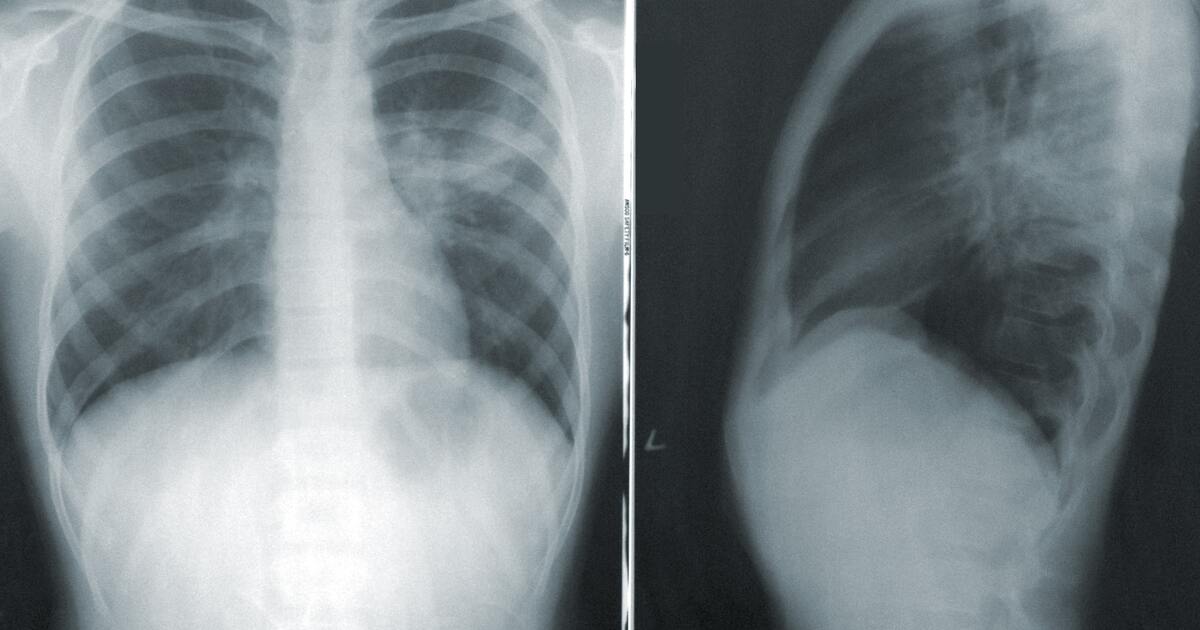

Рак лёгких считается одним из самых смертельных. Хотя его можно успешно вылечить на ранней стадии, очень мало людей проходят скрининг вовремя. А во время пандемии многие и вовсе отложили обследование на рак лёгких. Учёные из Темпльского университета в Филадельфии решили предложить телемедицинские скрининги на заболевание.

Исследователи сравнили данные по 673 пациентам, прошедших скрининг на рак лёгких до пандемии COVID-19, с данными по 440 пациентам, которые прошли телемедицинский скрининг с марта 2020 года. В итоге учёные пришли к выводу, что существенной разницы между двумя видами скрининга нет. То есть обследоваться можно не выходя из дома.